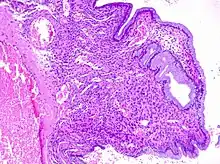

The cause is not known.[1] Risk factors include multiple prior births or sexually transmitted infections.[2] They tend to occur as single growth and are less than a centimeter in size; though may rarely be much larger.[1][2] Their color may vary from grey to red.[2] Most are not serious; thought, 0.2% to 1.5% are precancerous or cancerous, which mostly occur after menopause.[2] Diagnosis is generally suspected based on speculum examination and confirmed by histological examination.[2]

Cervical polyps can be seen during a pelvic examination as cherry-red or greyish-white projections from the cervical canal.[2] Diagnosis can be confirmed by a cervical biopsy which will reveal the nature of the cells present.[4]